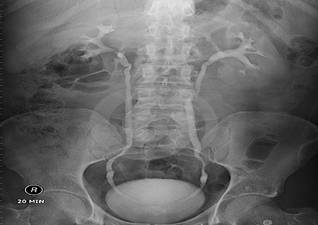

Tips:其中B超简单、无创,可以用来初步筛查,但由于受到腹部肠气干扰,对于没有扩张积水的输尿管及结石显影模糊不清,并且受到检查设备及检查医师的经验水平限制。X线造影可以直观的将结石的剪影投射在一张平片上,就像平常我们照相般反应结石及肾脏集合系统的大致情况。B超、X线造影的缺陷在于,其影像都是二维平面,看到结石也仅仅是一个片面,CT三维成像则能提供一个三维立体的图像,将肾脏及其中的结石直观立体地呈现在我们面前。这三者对于医师评估病情,决定手术方式、手术入路具有非常重要的作用。这就是为什么我们需要给每个结石病人做多种检查的原因,因为它们各有优缺点,互相验证,互相弥补,通过完善的检查,可以让患者结石的位置和形态在主刀医生的大脑中清晰的呈现!

X线造影